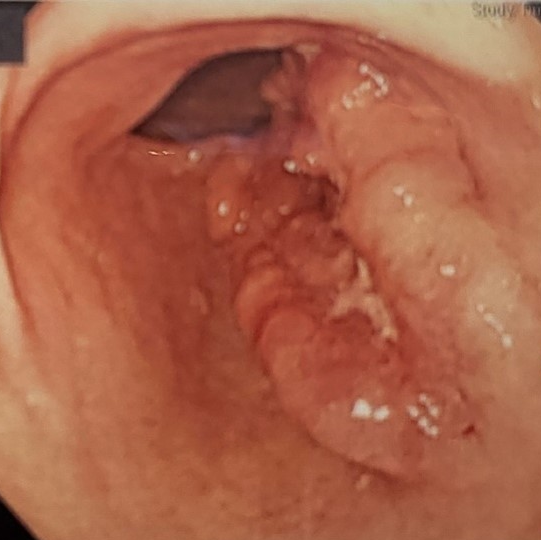

역류성식도염